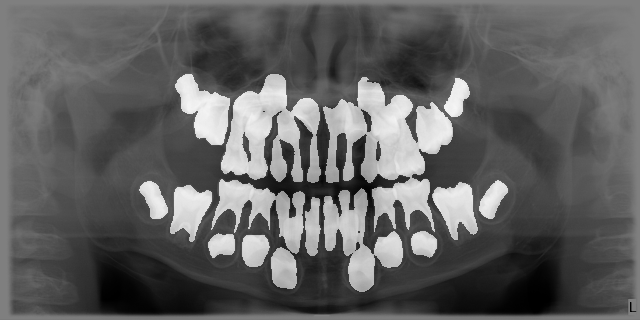

해상도 파노라마: 1333 × 800 pixels

1051개 (jpg) 1023px × 512px

1808장 1023px × 512px